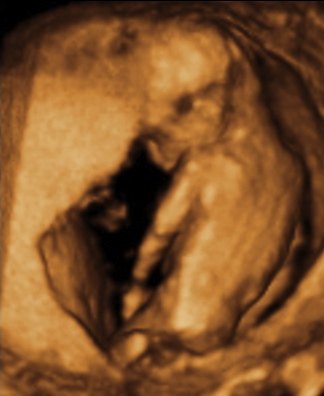

Det tror jeg på... Hehe... Sådan ser vores billeder fra kønsscanningen ihvertfald ikke ud fra uge 15 - og vi venter os en pige, så det er jo meget heldigt, at de ikke ligner hinanden